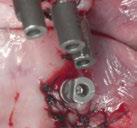

En las piezas 16 y 17 el paciente presentaba restauraciones atornilladas de metalcerámica sobre implantes oseointegrados. Se planificó realizar estas en una fase posterior a la rehabilitación de las piezas dentarias mediante flujo digital con bases de titanio y cuerpos de escaneo.

Figura 5. Impresión digital, vista superior derecha. Figura 3. Escaneado maxilar superior zona anterior. Figura 4. Impresión digital, vista superior izquierda.